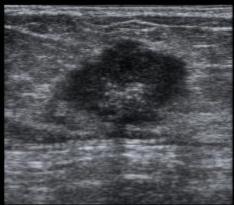

良性病变多是无血供的实性结节,而恶性结节由于对营养成分的过量摄取,往往其周围的血管数目、血供丰富,往最高血流速度大于20cm/s,血流阻力指数RI≥0.7,这是恶性结节的特征性表现。

结节内血供丰富,是恶性的征象。